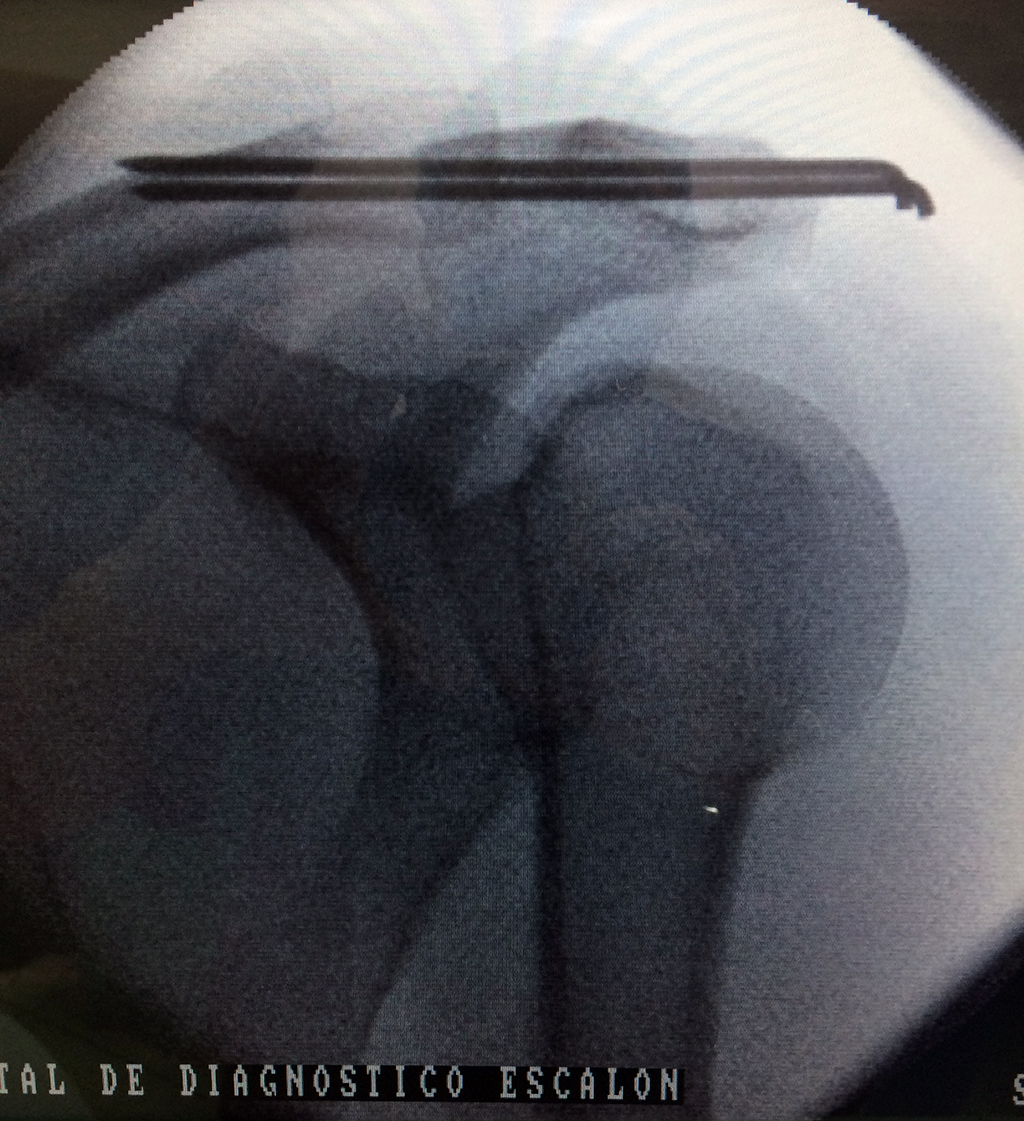

Calcaneo - Clavícula

La clavícula es un hueso largo, con forma de "S" itálica, situado en la parte anterosuperior del tórax. Junto con la escápula forman la cintura escapular. Se puede palpar por toda su longitud y se extiende del esternón al acromion de la escápula, siguiendo una dirección oblicua lateral y posterior.